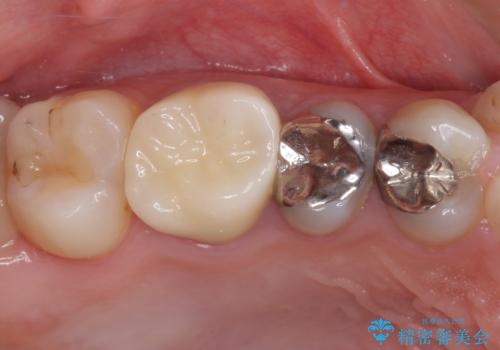

折角セラミッククラウンを装着するので、根管治療を行った後に補綴治療を行うこととしました。

他にも目立つ銀歯がありましたが、最も気にしている2本を優先して行うこととしました。

結婚式前にはクリーニングやホワイトニングを行い、その後他の歯を治療していく予定です。